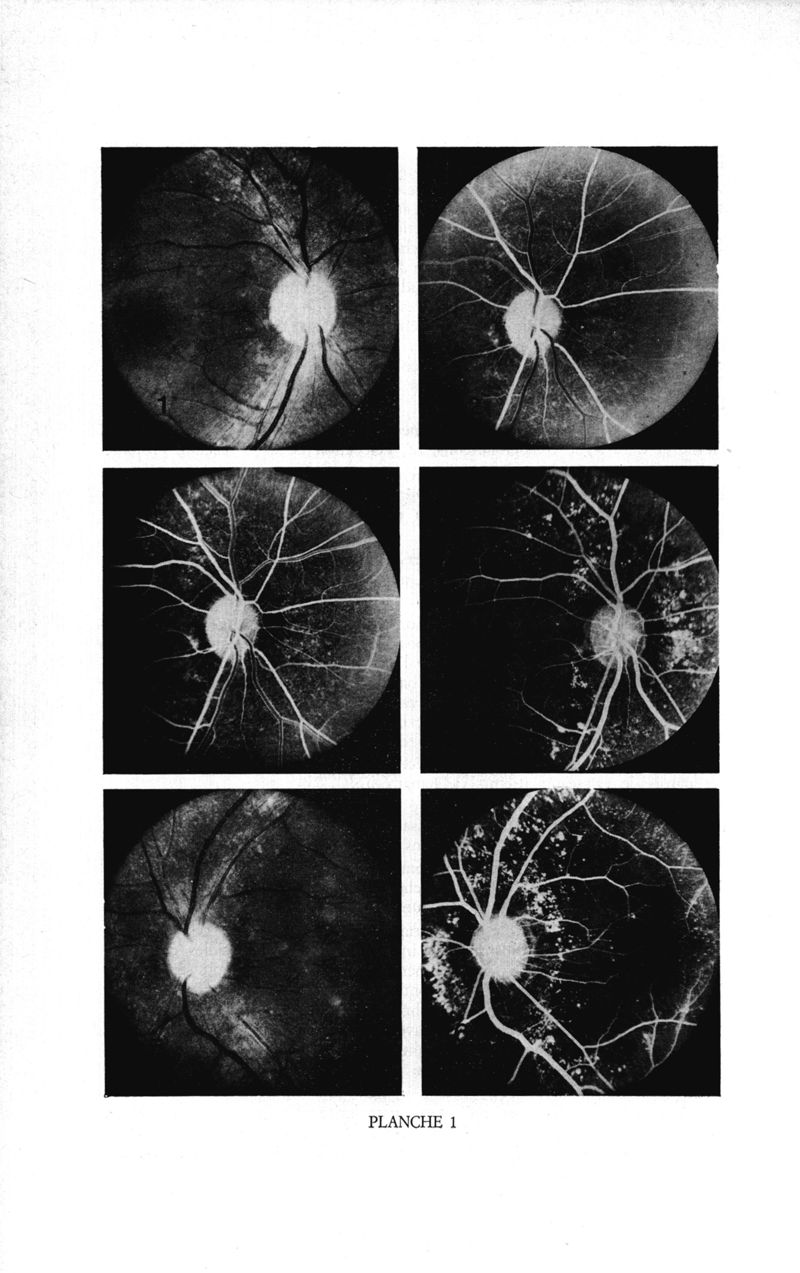

Médecine tropicale: revue française de pathologie et de santé publique tropicales

. - Marseille, 1974.